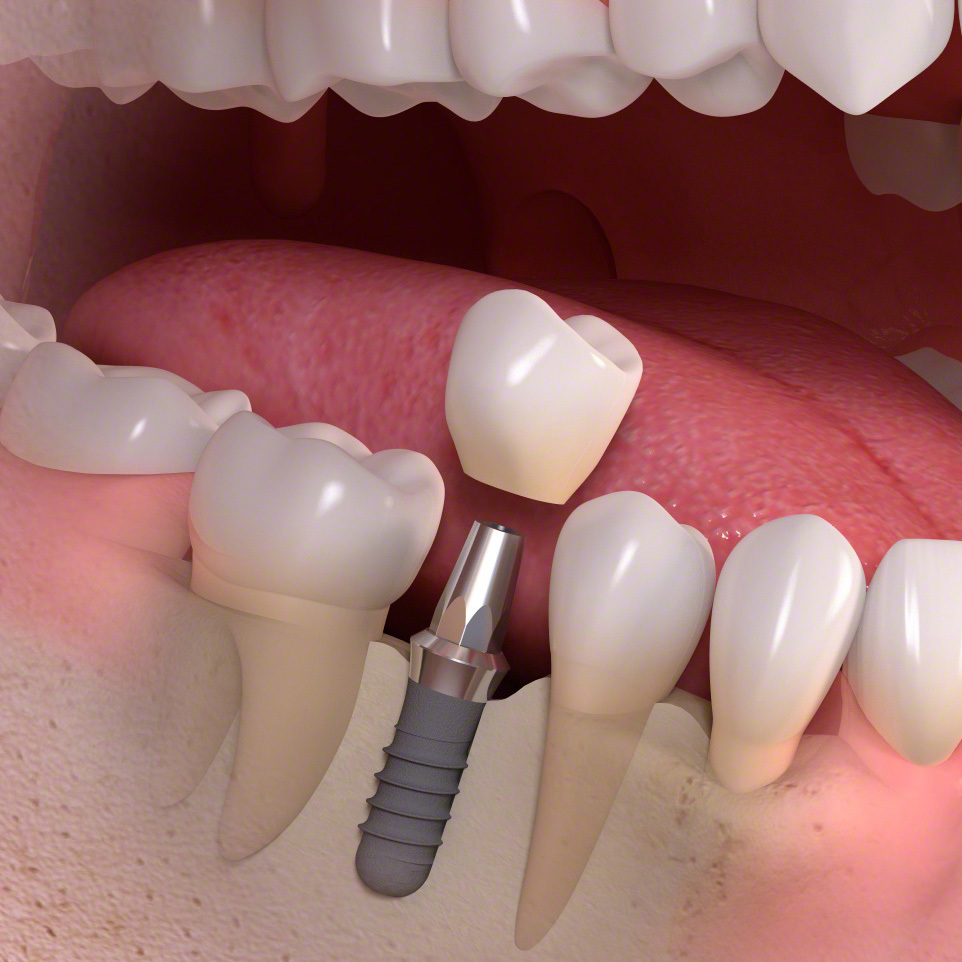

インプラントとは?

(通常のインプラント法)

歯科インプラントとは、歯を失った部分に人工歯根(主にチタン製)を外科的に埋め込み、その上にセラミックなどで作られた人工の歯を取り付けて、機能と見た目を回復する治療法です。

その後、一次手術としてインプラント体(フィクスチャー)を顎の骨に埋入し、数か月の治癒期間を経て骨としっかり結合させます。治癒後には二次手術を行い、歯肉からインプラントの上部構造を露出させます。なお、骨や歯肉の状態が良好な場合には、一次手術と二次手術を同時に行う「1回法」が選択されることもあります。

傷口が治った後に精密な型取りを行い、上部構造(人工歯)を製作・装着します。

インプラント構造

インプラントは、人工歯根(いわゆるインプラント)・支台(アバットメント)・人工歯(クラウン)、3つの部品で構成されています。